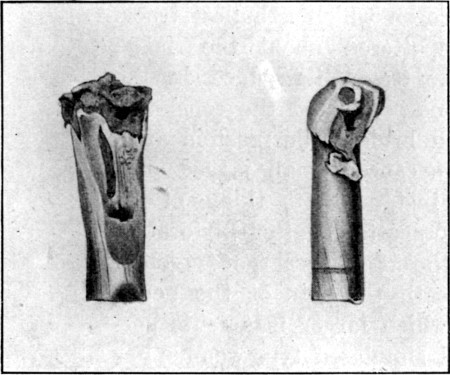

26. Sections of Four Bullets82

28. Four Mauser Ricochets 84

29. Mauser Ricochet, Disc Form 85

30. Fissured Mauser Mantle 86

31. Mausers Deformed by Impact on Femur 86

32. Apical Mauser Ricochet 87

33. Spiral Ricochet88